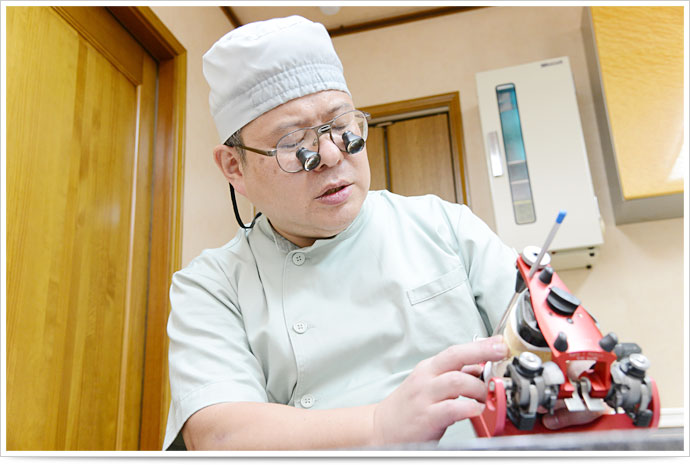

私は、日本顎咬合学会の会員であり、長年咬み合わせの研究をしてまいりました。実際、顎関節症の治療も数えきれないほど経験してきましたので、安心してご相談ください。